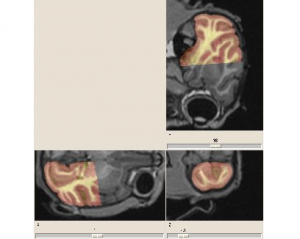

Atlas-based Brain Critical Structures Segmentation for Radiotherapy Planning

Brain radiotherapy must achieve two goals: the complete irradiation of the tumor, and the preservation of critical structures (brainstem, eyes, optical tracts, etc.). By customizing the shape of the irradiation beam and modulating the irradiation intensity, conformal radiotherapy allows to optimize the irradiation of the tumor and the critical structures. The planning of conformal radiotherapy requires accurate localizations of the tumor and the critical structures.

This work aims to delineate automatically the critical structures of the brain. In order to do this in a specific patient’s image, we use an anatomical atlas containing labels of the structures of the brain. This atlas is registered on the patient image by a global followed by a non rigid registration. The aim of this work is basically to develop a non rigid registration algorithm adapted to anatomical structures registration. The second goal is then to validate the method we propose using quantitative measures on manually delineated patients.

Brain shift modeling

It is usually the case in neurosurgery that pre-operative planning is based on the assumption that anatomical structures do not move between the image acquisition time and the operation time. In reality, the position of brain tissues changes during the operation and significantly decreases the accuracy of the planning made on the pre-operative image.

We propose a bio-mechanical approach based on a finite element model (FEM) of the brain to model this deformation. It takes into account the patient specificity and anatomical cerebral structures to predict the brain deformation.

This study is based on the analysis of 7 cases of Parkinson operations, realized at La Pitie Salpetriere hospital (Paris). It focuses on modeling the static effects of gravity on the brain deformation after dura-mater opening, visible on the post-operative MRI.